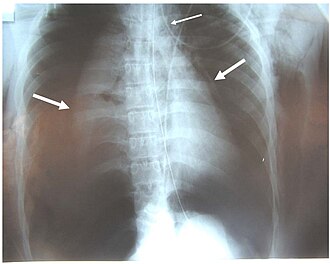

- radiografiju srca i pluća sa spirometrijom,

- radiografiju paranazalnih šupljina,